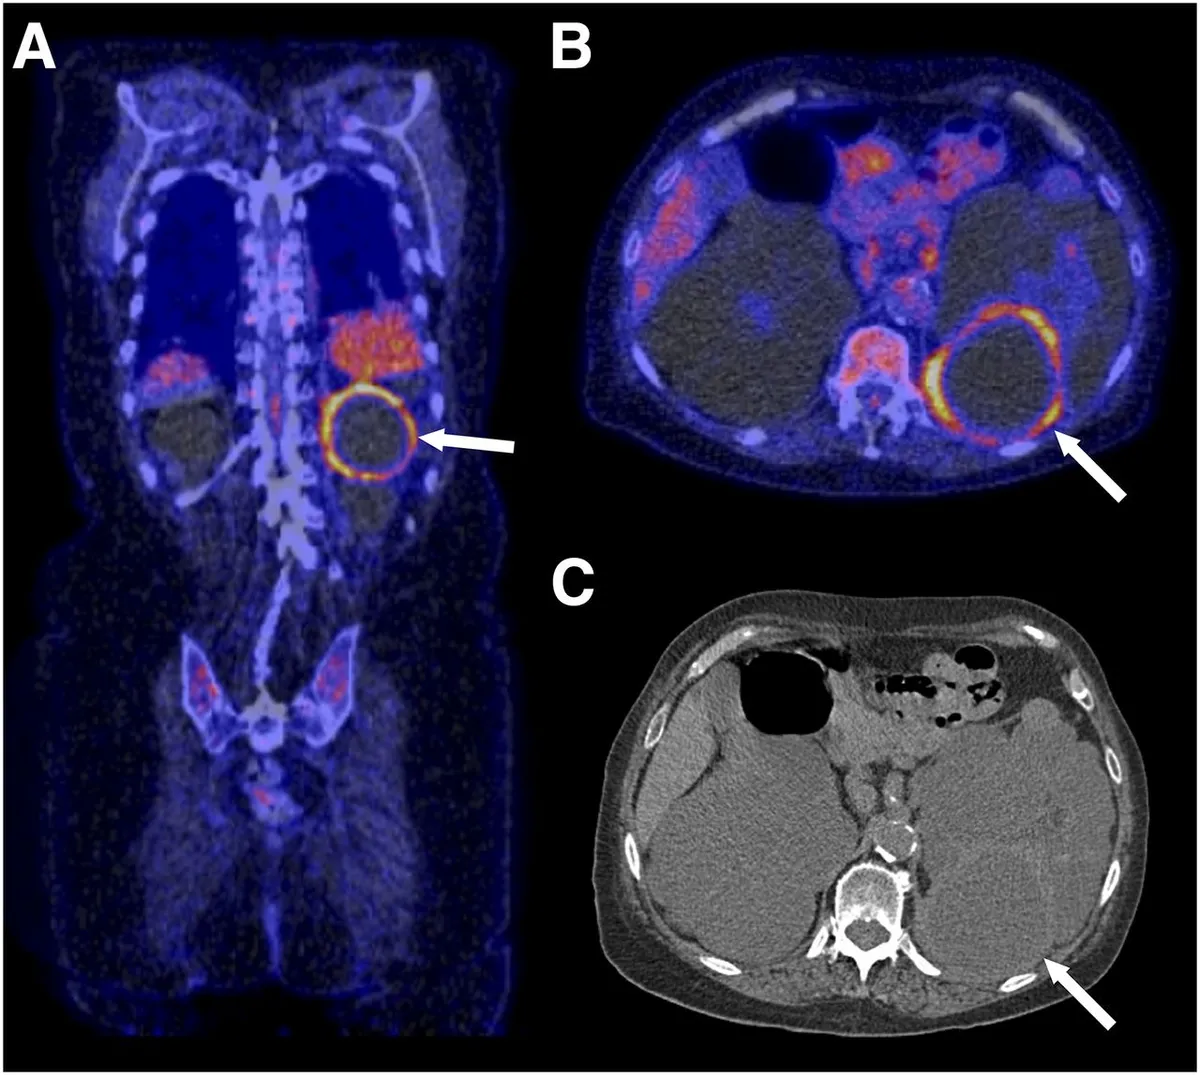

DRPAD além do Tolvaptana: Novas Perspectivas Terapêuticas nas Diretrizes KDIGO 2025

Além do tolvaptana, as diretrizes KDIGO destacam a importância de medidas não farmacológicas e abordagens complementares no manejo da DRPAD, como controle rigoroso da pressão arterial, redução de ingesta de sal e aumento de ingestão hídrica. Estudos em andamento também avaliam terapias-alvo envolvendo vias do mTOR, cAMP e inflamação. O manejo multidisciplinar permanece essencial para retardar a progressão da doença e melhorar a qualidade de vida.

Uso do Tolvaptan na DRPAD: O Que falam nas Novas Diretrizes KDIGO 2025?

As novas diretrizes KDIGO para a Doença Renal Policística Autossômica Dominante (DRPAD) atualizam os critérios de elegibilidade para o uso de tolvaptana, com ênfase na estratificação do risco de progressão rápida. O documento reforça a individualização da terapia com base em subclassificação por imagem (Mayo Clinic) e função renal. A incorporação prática dessas recomendações pode otimizar o manejo e retardar a progressão da DRC nesses pacientes.